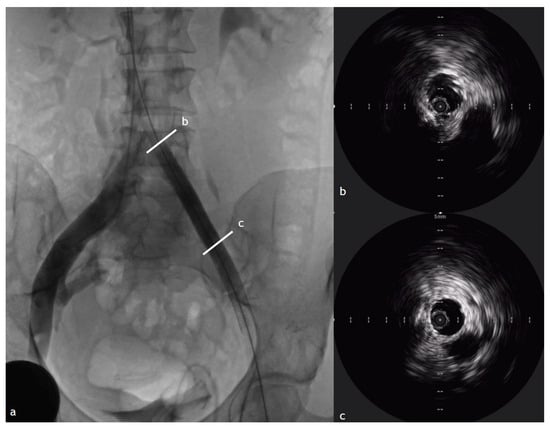

6. IVUS in Venous Stenting Procedure